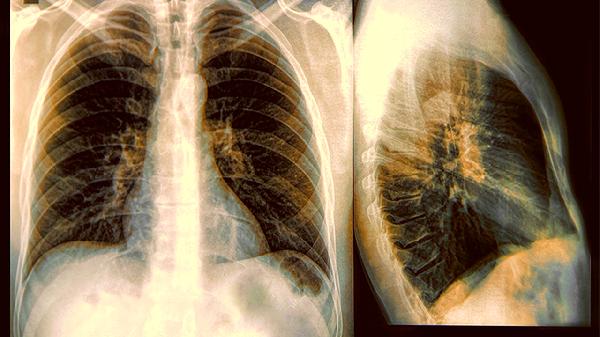

2.体检单上的尺寸密码

5mm以下的"小不点"基本可以定期观察,超过3cm的"大块头"才需要重点关照。B超报告里"形态规则""边界清晰"这些词,往往比尺寸更值得划重点。